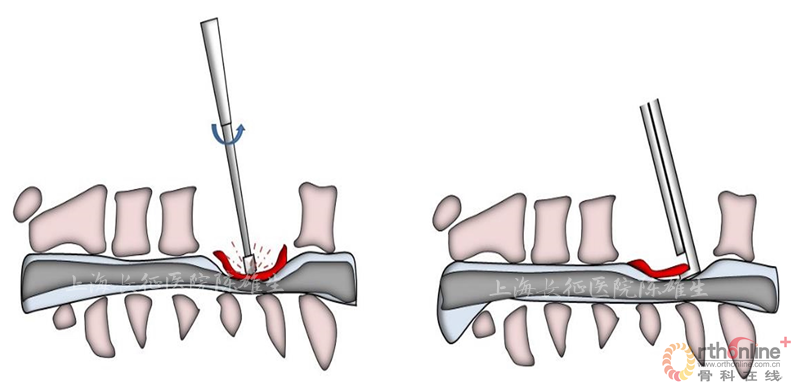

2.3 磨钻的损伤

磨钻等工具将骨化物打磨成薄片时对脊髓压迫最严重区域的震荡和热作用加重脊髓损伤(图7)。甚至磨钻等工具突破骨化物对脊髓直接造成损伤。(图8).

图7

图8